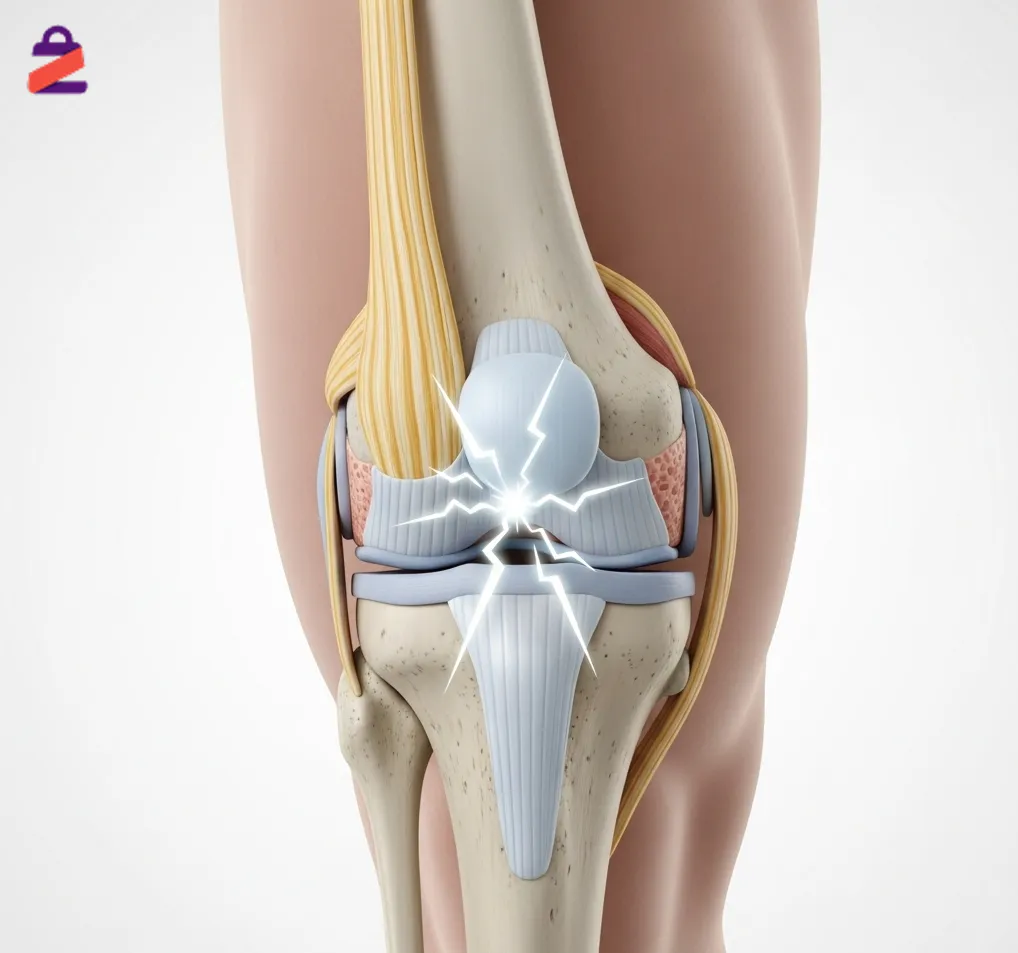

علت دررفتگی زانو چیست؟ برای درمان آن چه کنیم؟

دررفتگی زانو یعنی وقتی استخوانهای ران و ساق پا از جای اصلی خود در مفصل زانو بیرون میآیند و زانو کاملاً جابجا میشود. این اتفاق معمولاً بر اثر ضربههای خیلی شدید مثل تصادف، افتادن از ارتفاع یا فشار زیاد در ورزش رخ میدهد. دررفتگی زانو با درد و ورم زیاد همراه است و گاهی میتواند […]